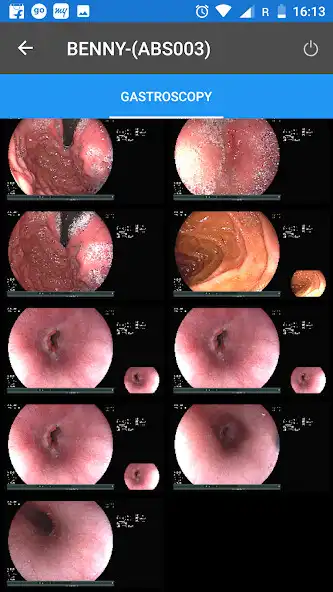

MediView is designed to optimize both time and cost in today's changing and demanding health care scenario. The robust feature coupled with security increase your workflow efficiency by managing patient reports, image and data that enhance patient care.Updates: